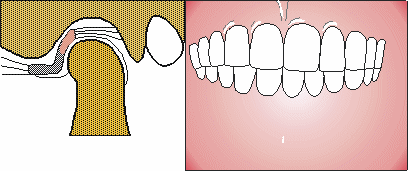

Maloclusión

Afecta el tipo de mordida con la función y perfilamiento del rastro.

No solo se trata de la forma y alineación de los dientes